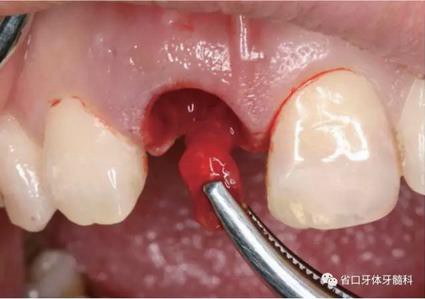

(1)微創(chuàng)拔牙及即刻種植:術(shù)前拍攝口內(nèi)照及實(shí)施牙周基礎(chǔ)治療。常 規(guī)消毒鋪巾阿替卡因局麻下微創(chuàng)拔除上頜右側(cè)中切牙,搔刮拔牙窩及根尖肉 芽組織。探測牙槽骨唇側(cè)骨壁及鄰面牙槽嵴完整,牙齦無撕裂。不翻瓣下于上頜右側(cè)中切牙缺隙近遠(yuǎn)中中點(diǎn)的腭側(cè)牙槽骨及根方定位,按照逐級預(yù)備的原則,緊貼牙槽窩腭側(cè)骨壁制備種植窩洞,植入Zimer®3.7mm×13mm TSV種植體1顆,植入扭矩>35N·cm,以O(shè)sstell測量種植體的ISQ值為68。 種植體平臺(tái)位于唇側(cè)齦緣中點(diǎn)下3mm,與唇側(cè)骨壁內(nèi)側(cè)面形成的跳躍間 隙約2mm,置入Bio-Oss®細(xì)顆粒骨粉0.25g,上愈合基臺(tái)關(guān)閉創(chuàng)口。術(shù)后 CBCT檢查顯示:種植體利用牙槽窩根方骨質(zhì)固位,緊貼牙槽窩腭側(cè)骨壁, 其唇側(cè)面與牙槽窩唇側(cè)骨壁的內(nèi)側(cè)面所形成的跳躍間隙(約2mm)可見顆 粒狀顯影物充填。牙槽窩的唇側(cè)骨壁及唇側(cè)倒凹無缺損穿孔。

圖9 探測唇側(cè)骨壁完整

圖10 唇側(cè)骨壁完整